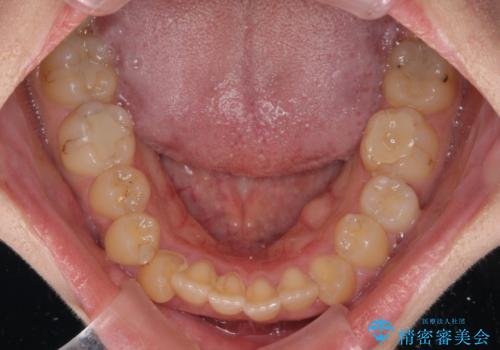

八重歯を抜歯矯正でスッキリと メタルブラケットでの矯正治療

- 八重歯と上下前歯のでこぼこを気にして来院された患者様です。

上下前歯部叢生のスペース獲得のため、上下顎左右小臼歯各1歯(計4本)と全ての親知らずを抜歯して、矯正治療を行うこととしました。

八重歯とは別に上下前歯の隙間という問題もありました。こちらは舌突出癖によるものと考えられたため、舌のトレーニングをしっかりと行っていただきました。